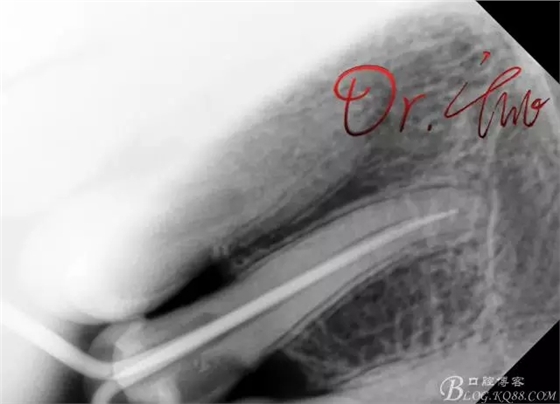

初診照

拍片確定長度

第一次試主尖

第二次試主尖

根充